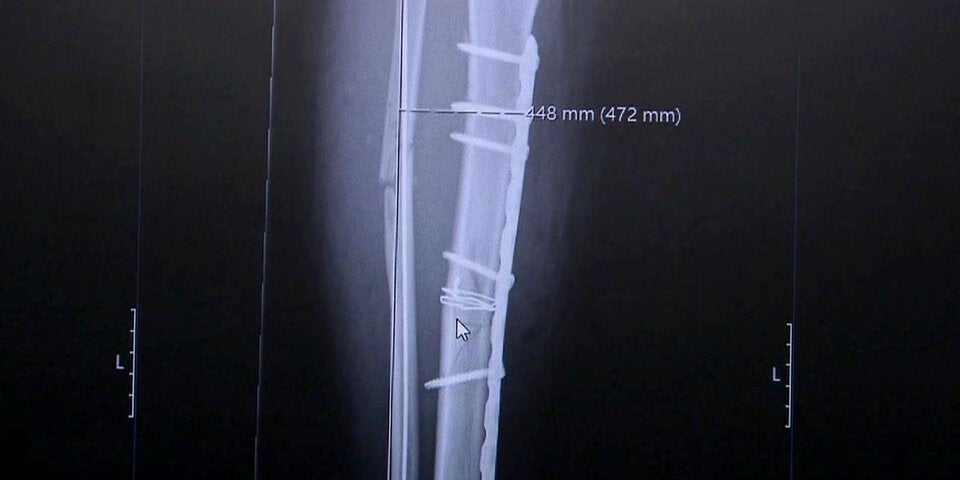

Abtransport im Helikopter, in der Klinik in Schruns wird alles für die Operation vorbereitet. Für Ortlieb ist es bereits die 20. ihrer Karriere. Schenk, der schon Ortliebs Knie nach dem letzten Horrorsturz vor drei Jahren in Crans Montana zusammengeflickt hatte, schildert den Eingriff: „Das Schienbein haben wir, wie man sagt, verplattet, das Wadenbein mussten wir leider offen einrichten und danach verdrahten."

Beim Besuch eines ORF-Kamerateams entfernt Nina den Verband und zeigt die lange Operationsnarbe, die sich fast über den ganzen Unterschenkel zieht. "Die ersten Tage waren schwierig", gibt die Vorarlbergerin zu. "Aber inzwischen spür ich, wie es bergauf geht - mental und körperlich."